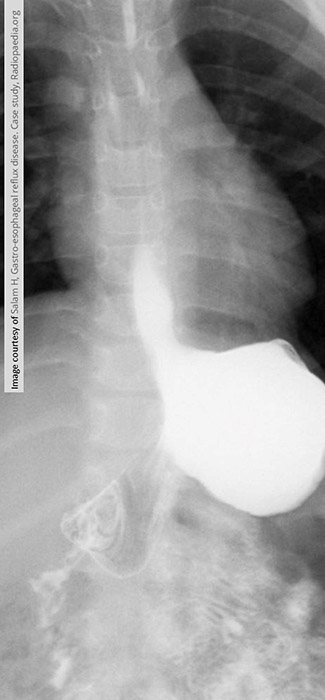

What is the standard imaging study for GERD?

Fluoroscopic barium swallow with UGI.

What are the early radiographic changes in GERD?

Mild esophageal dilation and reduced peristalsis.

What is the late-stage radiographic appearance of GERD?

Smooth, tapered narrowing of distal esophagus due to scarring; Barrett’s esophagus appears stomach-like.